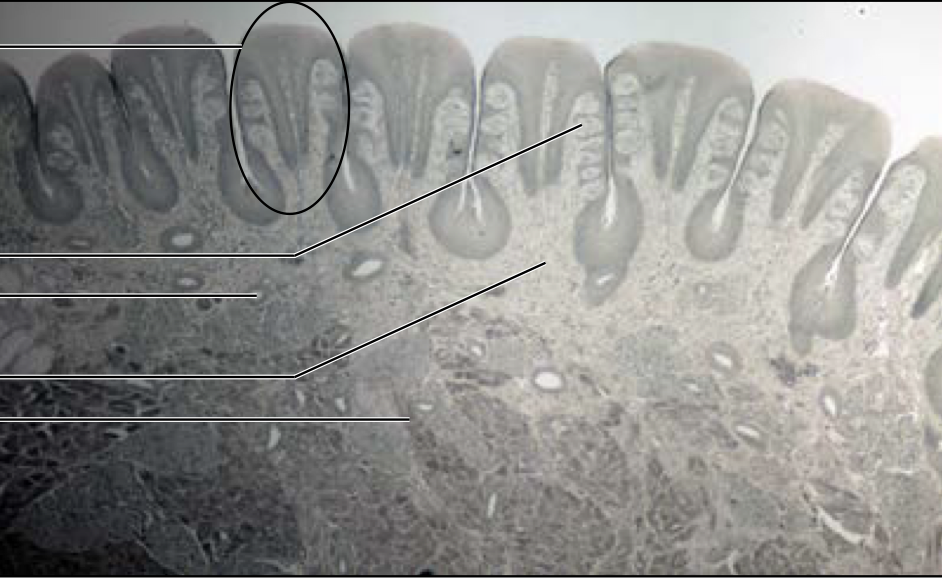

New cards

What can be seen in the slides of the duodenum?

Brunners glands (alkaline) in submucosa

59

What can be seen in the ileum and colon slides?

Peyers patch's in submucosa

60

On lips...

Keratin on outer region and glands on inner region

61

What can be seen on colon slides?

Thick layer of submucosa and large goblet cells

term image

Stomach

contain gastric pits and glands

82

Duodenum

brunners gland and goblet cells

83

Jejunum

84

Ileum

85

Colon